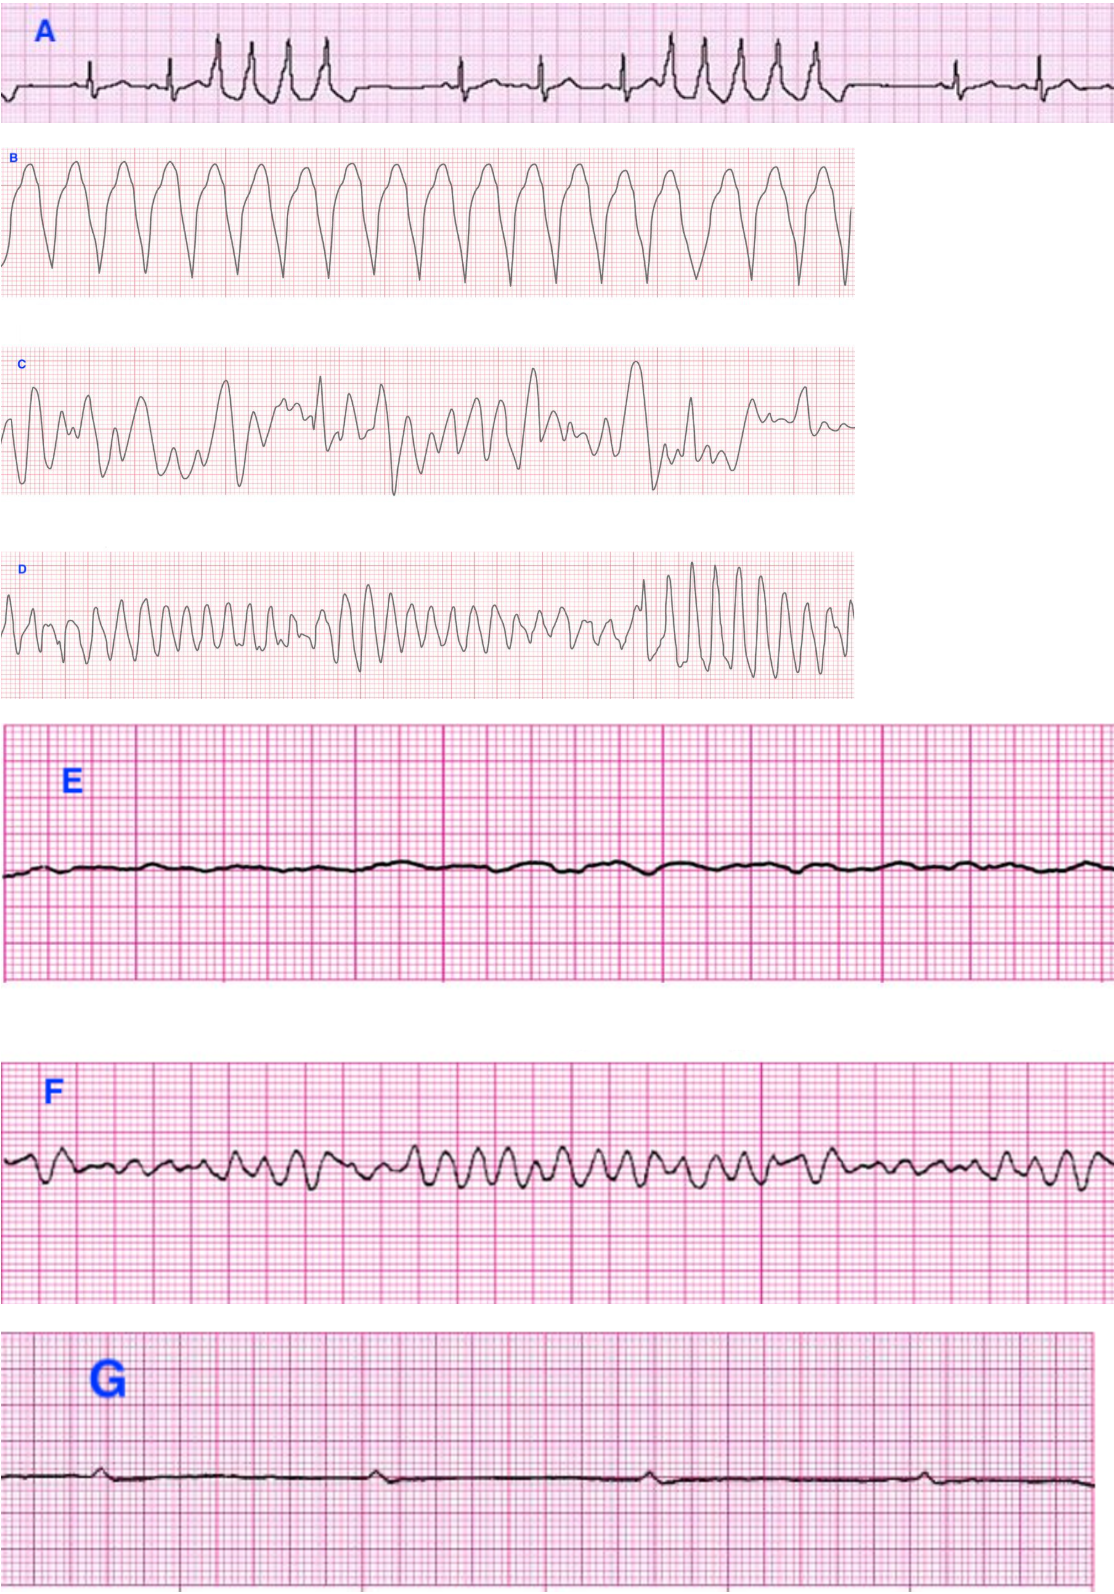

Match the following ECG strips to the correct ventricular rhythms:

A. Nonsustained monomorphic VT

B. Sustained monomorphic VT

C. Polymorphic VT

D. Torsades de pointes

E. Fine wave VF

F. Coarse wave VF

G. Ventricular standstill